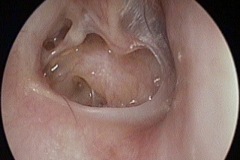

Perforation